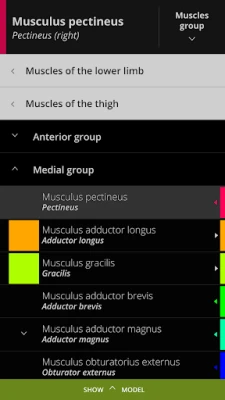

Using our cutting-edge 3D model, which is one of the most detailed in the world, ANATOMYKA allows you to get up close with human anatomy in all its breathtaking complexity on more than 13,000 anatomical structures with more than 500 pages of medical descriptions. Now in English, Spanish, Italian, Polish, Russian, Czech, Slovak and Hungarian localization.

In the ANATOMYKA app, each anatomical system, organ and part is accompanied by detailed information about its structure, hierarchy, regions, including information about organs, clinical notes, related organs (vascular supply, innervation, syntopy) and a general description.

Color-coded organs allow users to view high-resolution anatomical structures supplemented by informative descriptions from a comprehensive textbook ‘Memorix Anatomy’. These are arranged into a proper anatomical hierarchy, meaning learning is structured and easy to understand.

- User-friendly interface: Zoom, rotate, scale, colorize, isolate, select, hide, and fade all anatomical structures

- Multiple selection: Select multiple organs and structures at once

Color-coded organs allow users to view high-resolution anatomical structures supplemented by informative descriptions from a comprehensive textbook ‘Memorix Anatomy’. These are arranged into a proper anatomical hierarchy, meaning learning is structured and easy to understand.